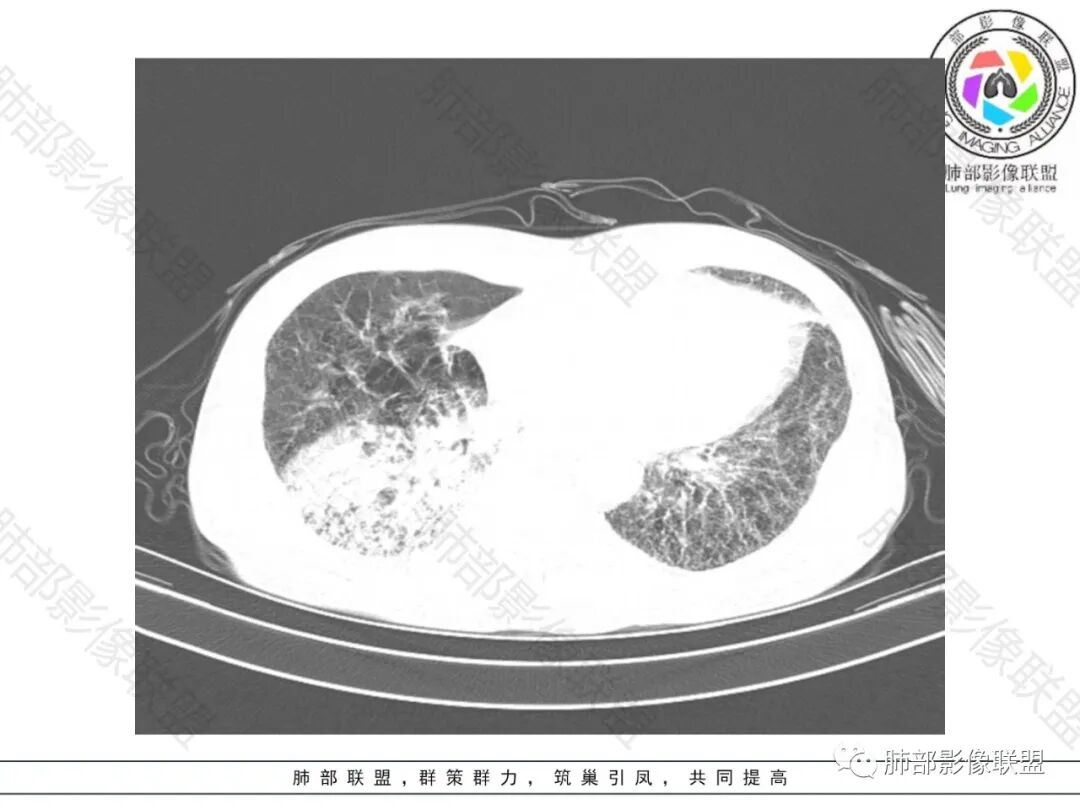

双肺慢支肺气肿。右肺下叶大片状影,支气管狭窄,枯枝状。间杂网格状影,实变影(与胸膜糊墙),叶间裂膨隆。右肺门增大。增强后右下肺片状影内血管束失去正常形态,边缘模糊。实变影不均匀强化。纵隔及右肺门多组淋巴结肿大,其中右侧10、11、12组淋巴结肿大内见液化。考虑肺炎型肺癌并感染?不典型结核待除外。左下小片影?(层面不全)。

老年男性,反复咳嗽咳痰喘憋8年,加重10天,发热半天。白细胞计数明显升高(存在细菌感染可能),CEA、CA19—9升高(肺癌或间质性肺疾病引起可能)。痰培养见肺克。CT;双肺弥漫小叶间质、中轴间质增厚,胸膜下肺气肿,右肺门及右下叶可见实变影,边界模糊,内支气管走形僵硬,部分见蜂窝样改变,增强后实变区可见低密度区(粘液?),叶间裂膨隆,纵隔及右肺门见肿大淋巴结,右肺门淋巴结内见坏死。存在感染,但单纯感染难以解释支气管走行僵硬、实变内的低密度病灶,考虑恶性伴感染,肺炎性肺癌或黏液腺癌。

病史八年,慢支病史,两肺中轴间质及小叶间隔增厚,可见胸膜下线,提示有间质性肺病ulp,右下肺大片实变,叶间裂膨隆,纵隔淋巴结肿大,实变内GGO以网挌为中心,强化有血管造影征,实变内支气管走行僵直〈枯树枝征)并扭曲扩张,可见低密度粘液拴,综合考虑为1,右下肺炎性肺癌,粘液腺癌可能性大,2,uip

2.影像表现:肺气肿背景,右肺下叶呈现明显网格影及蜂窝影、枯枝征,边缘膨隆、叶间裂向前方推移。病灶密度不均,前份见不规则片状实性密度区,实性部分轻度强化,边界不清,周边特征掩盖不清。支气管主要分支显示,呈枯枝征。纵隔窗病灶密度偏低,病灶内血管影边缘稍显模糊,未见明显液化坏死区。

余双肺未见明显结节影。

右侧肺门淋巴结肿大,中央低密度;纵隔见轻度增大淋巴结。

3.综合分析:临床方面:慢性病程、急性发作,呼吸道症状伴发热,炎性指标升高,提示存在感染可能;CA199升高,但相对特异性不高。影像双肺气肿,右肺下叶蜂窝状改变明显,夹杂实变密度区,支气管相关但未见阻塞,较常见于感染性病变,如G-杆菌感染等。蜂窝影什么时候出现我们不得而知,实变区周边特征掩盖不清。

前后三月余病灶变化不明显,右肺门异常肿大淋巴结让人警惕恶性病变可能性。

因为有肺气肿背景、有蜂窝,周边特征及张力等都不能作为判断依据或参考。单肺叶蜂窝影伴实性密度区被确诊为肺腺癌的例子已不少见,敬请留意。